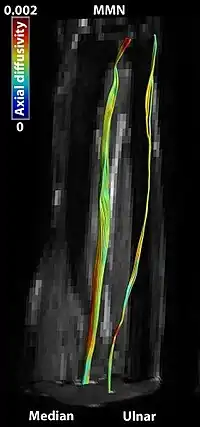

Multifocal motor neuropathy (MMN) is a progressively worsening condition where muscles in the extremities gradually weaken. The disorder, a pure motor neuropathy syndrome, is sometimes mistaken for amyotrophic lateral sclerosis (ALS) because of the similarity in the clinical picture, especially if muscle fasciculations are present. MMN is thought to be autoimmune. It was first described in the mid-1980s.[1]

The diagnosis of MMN depends on demonstrating that a patient has a purely motor disorder affecting individual nerves, that there are no upper motor neuron (UMN) signs, that there are no sensory deficits, and that there is evidence of conduction block. These criteria are designed to differentiate the disorder from ALS (purely motor but with UMN signs), the Lewis-Sumner Syndrome variant of Chronic inflammatory demyelinating polyneuropathy (CIDP) (similar to MMN but usually with significant sensory loss), and "vasculitis" (a type of multiple mononeuropathy syndrome caused by inflammatory damage to the blood vessels in nerves that also causes sensory and motor symptoms).

A neurologist is usually needed to determine the diagnosis, which is based on the history and physical examination along with the electrodiagnostic study, which includes nerve conduction studies (NCS) and needle electromyography (EMG). The NCS usually demonstrate conduction block. This can be done by showing that the nerve signal cannot conduct past a "lesion" at some point along the nerve. For example, if the nerve is blocked in the forearm, an electrical impulse can easily get from the wrist to the hand if the stimulus is placed at the wrist. However, the signal will be blocked from reaching the hand if the stimulus is applied at the elbow. In MMN, sensory conduction along the same path should be normal. The EMG portion of the test looks for signals in the way muscles fire. In MMN it will most likely reveal abnormalities suggesting that some percentage of the motor axons has been damaged. Laboratory testing for GM1 antibodies is frequently done, and can be very helpful if they are abnormal. However, since only a third of patients with MMN have these antibodies, a negative test does not rule out the disorder. Spinal fluid examination is not usually helpful.